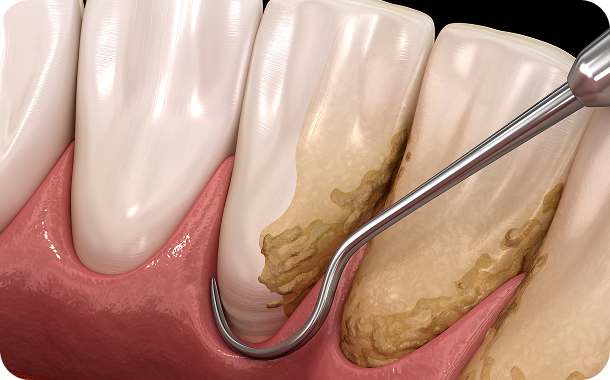

단순한 치료를 넘어 일상의 완성을 설계하는

통합 진료 솔루션

단순한 치료를 넘어 환자의 마음을 헤아리는 것에서 연세아이돌치과의 진료는 시작됩니다.

치과교정과 전문의의 심미적 안목과 통합치의학과 전문의의 포괄적 진단이 만나는 곳.

연세아이돌치과교정과의 일반진료는 단순히 질환 부위만을 바라보지 않습니다.

치아 하나가 전체 구강 구조와 조화를 이루는지,

환자분의 식습관과 생활 패턴에 장기적으로 어떤 영향을 미칠지까지 치밀하게 계산합니다.